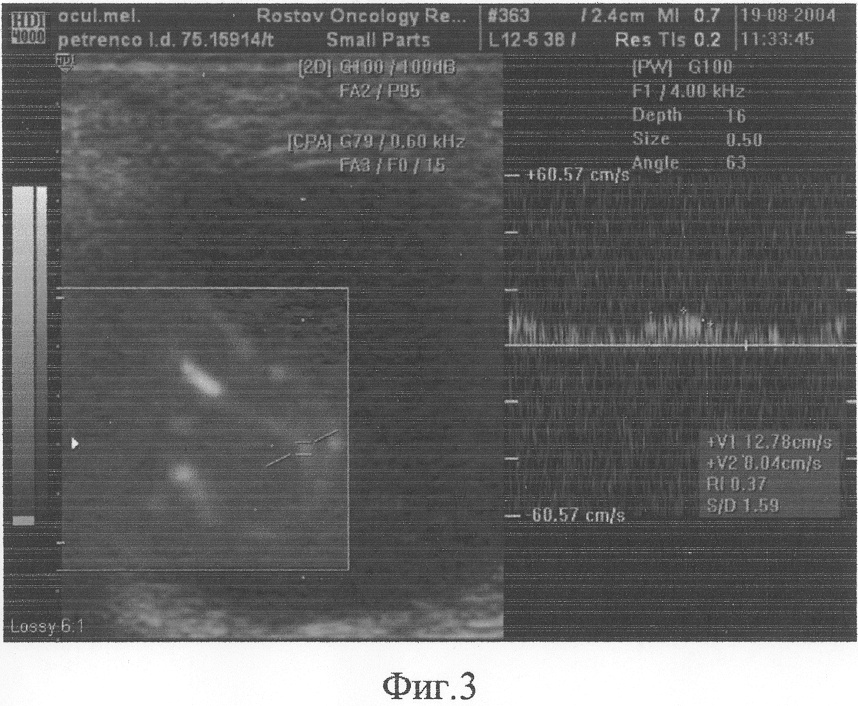

УЗИ от 19.08.04. – правое глазное яблоко нормальной формы и размера. Подвижность полная. В В-режиме определяется в проекции основания с переходом на латеральную стенку, гиперэхогенное образование 1,35×1,24 см с ровными, четкими контурами. По задней стенке с переходом на область образования лоцируется двойной контур отслойки сетчатки. При энергетическом доплеровском картировании (ЭДК) определяется выраженное развитое сосудистое русло с артериальным низкорезистентным неоангиокровотоком смешанного типа (центрального и периферического). При мультилокусной доплерометрии в трех сосудах патологического образования показатели максимальной артериальной скорости внутриопухолевого сосудистого русла составили: Vmax – 8,52 см/с, 18,46 см/с, 12,78 см/с. Индекс периферического сосудистого сопротивления меньше 0,5 (RI)-028, 0,46, 0,37 (фиг.1-3), что явилось специфическим доплеровским признаком.

Заключение: Меланома хореоидеи правого глаза с вторичной отслойкой сетчатки. Диагноз был подтвержден интраоперационно и гистологически. 22.08.04 – призведено оперативное удаление правого глаза. Гистологический анализ №765441-081: меланома правого глазного яблока, смешанноклеточный вариант.